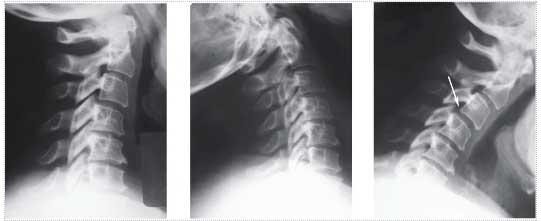

| 14:31, 14 августа 2017 | Bol spina16.jpg (файл) | 12 КБ | Рентгенография шейного отдела позвоночника. Нестабильность ПДС С3-С4 при сгибании в шейном отделе позвоночника - смещение С3 кпереди на 3 мм | 1 | |

| 14:29, 14 августа 2017 | Bol spina14.jpg (файл) | 10 КБ | Рентгенография шейного отдела позвоночника. Отмечается субхондральный остеосклероз (1), снижение высоты межпозвоночного промежутка (2), ф… | 1 | |